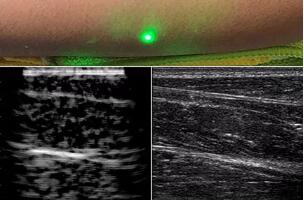

目前,研究人員已經(jīng)與健康的志愿者測試了他們的系統(tǒng):從半米遠(yuǎn)處掃描了他們的前臂,并將這些結(jié)果與傳統(tǒng)超聲的結(jié)果進(jìn)行了比較。他們能夠觀察到深達(dá)6厘米的組織,并能看到肌肉,脂肪和骨頭,并報(bào)告其結(jié)果可與標(biāo)準(zhǔn)超聲相媲美。

研究人員用一種激光裝置測試了這個(gè)想法,該裝置使用一個(gè)波長為1,550納米的脈沖激光來產(chǎn)生聲波,并使用第二個(gè)連續(xù)激光,調(diào)諧到相同的波長以遠(yuǎn)程檢測反射的聲波。第二個(gè)激光器是靈敏的運(yùn)動(dòng)檢測器,可測量聲波從肌肉,脂肪和其他組織反射回來而引起的皮膚表面振動(dòng)。反射的聲波產(chǎn)生的皮膚表面運(yùn)動(dòng)會(huì)導(dǎo)致激光頻率發(fā)生變化,這種變化可以測量。通過機(jī)械掃描人體上的激光,科學(xué)家可以獲取不同位置的數(shù)據(jù)并生成該區(qū)域的圖像。